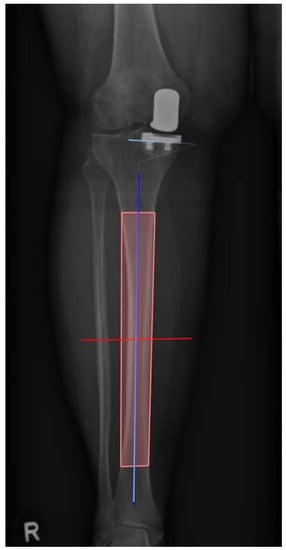

Within one year postoperatively, the clinical and radiological follow-up of the patients took place. Patients were routinely examined and surgery sites were controlled. Standard weight bearing radiographs in lateral projection as well as long-leg radiographs were taken. Subsequently, the inclination of the tibial component was determined. Radiographic analysis was performed in Horos for Mac, Version 3.3.6 [11]. First, the anatomical axis of the tibia was determined in the a.p. long-leg radiographs according to Paley [12]. Four points of the two cortices were marked, two in the proximal and two in the distal metaphysis, each with one on the lateral and one on the medial corticalis, resulting in a rectangle shape. Based on this, the software automatically calculated the center of the four landmarks and thus the longitudinal axis. Following that, the angle of the tibia component was calculated from the previously determined axis and the lower edge of the tibial implant. Figure 4 represents the measurement process. Two points on the medial and two on the lateral cortex were marked and thus the longitudinal axis was calculated. Next a tangent was drawn to the lower border of the tibial component and thus the medial inclination calculated between tangent and longitudinal axis.

Figure 4. Illustration of the measurement process. Two points on the medial and two on the lateral cortex were marked and thus the longitudinal axis was calculated. Next a tangent was drawn to the lower border of the tibial component and thus the medial inclination calculated between tangent and longitudinal axis. In this case of group 1 the angle was 87.4° varus (R = right side).